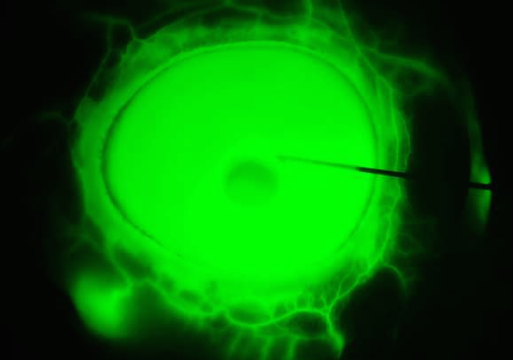

• Regionally Discrete Aqueous Humor Outflow Quantification Using Fluorescein Canalograms

• RT Loewen, EN Brown, P Roy, JS Schuman, IA Sigal and NA Loewen

• PLoS ONE, 11(3), e0151754, March 2016.

image